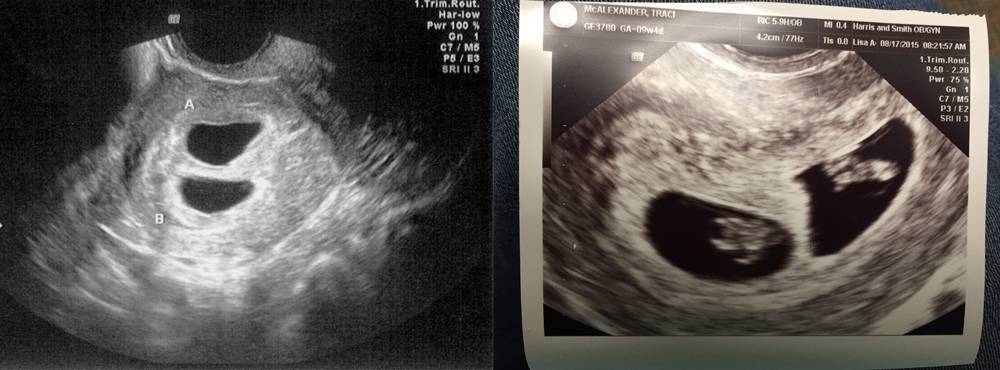

Признаки многоплодной беременности

- Обязательно УЗИ показывает у всех беременных двойней два плодных яйца

УЗИ-3Д в первом триместре беременности

В первом триместре закладываются основные органы и системы малыша. Женщина, посетив УЗИ 3D, убеждается, что беременность протекает хорошо и узнает ее точный срок. На экране видно, где прикрепился эмбрион, нет ли пороков развития и предлежания плаценты. Определяется число плодов. Это позволяет выбрать правильную тактику ведения беременности.

Исследование проводят на 11-13 неделе, когда длина эмбриона достигает 45 мм. Врач оценивает параметры развития зародыша и сравнивает их с нормальными. Определяется рост малыша, развитие костей конечностей и симметричность полушарий мозга. Оценивается состояние сосудов плаценты, тонус матки и состояние ее зева. Обязательно оценивается достаточность околоплодных вод — амниотический индекс.